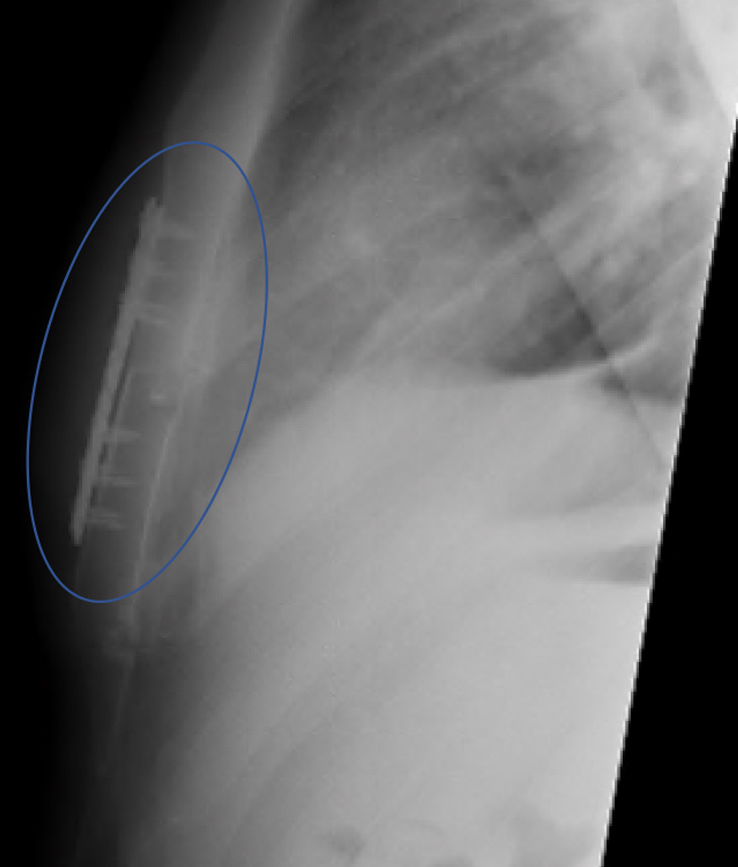

Chest X-ray from the side and front showing multiple rib plates following Open Reduction Internal Fixation after a significant rib injury.

Sternal x-ray following open reduction & internal fixation (blue ring)